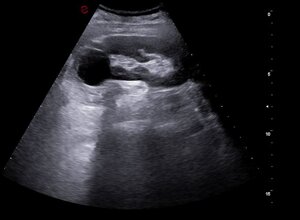

ECOGRAFIA ADDOME